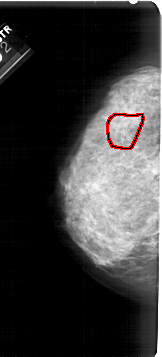

A_1939_1.LEFT_MLO

LEFT_MLO LINES 5491 PIXELS_PER_LINE 2851 BITS_PER_PIXEL 12 RESOLUTION 43.5 OVERLAY

FILE: A_1939_1.LEFT_MLO.OVERLAY

TOTAL_ABNORMALITIES 1

ABNORMALITY 1

LESION_TYPE CALCIFICATION TYPE AMORPHOUS DISTRIBUTION SEGMENTAL

ASSESSMENT 4

SUBTLETY 3

PATHOLOGY BENIGN

TOTAL_OUTLINES 1

BOUNDARY